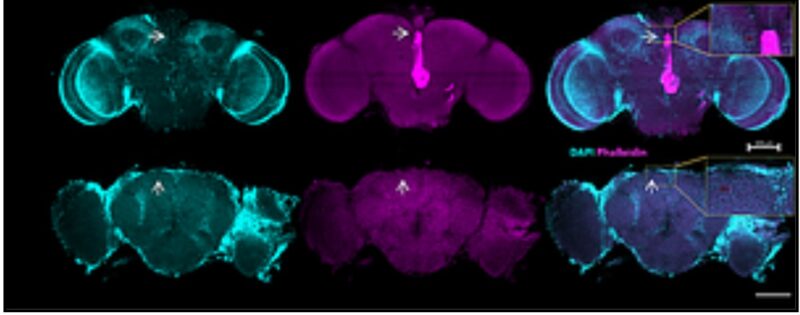

צילום מיקרוסקופי: בשורה העליונה-צילום מוח של זבוב רגיל, ובשורה התחתונה מוח של זבוב עם ניוון עצבי, המראה חורים במוח". קרדיט: שי קלוקסי

פרופ' טויבר וצוותה הוכיחו שנזק זה אינו בלתי הפיך. במודל שהתבסס על זבובים חסרי סירטואין 6, הם הצליחו לעכב את האנזים TDO2 ובכך מנעו באופן משמעותי הן התדרדרות נוירו-מוטורית והן היווצרות של בועיות  ברקמת המוח, מה שמצביע על חלון הזדמנויות טיפולי משמעותי.